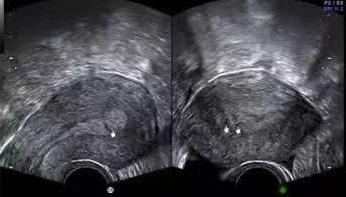

图 |经阴道三维超声显示宫腔粘连更清晰、更直观

相比常规阴超,经阴道三维超声不仅增加了子宫冠状切面图像,能清晰地显示宫腔内结构、肌层及宫底结构的立体形态,轮廓大小、表面特征,空间位置关系;还可以不受方向限制,从多个方位对内膜病变进行观察,更加直观的展示可疑部位与周围组织的关系,帮助医师更好地判定病情。